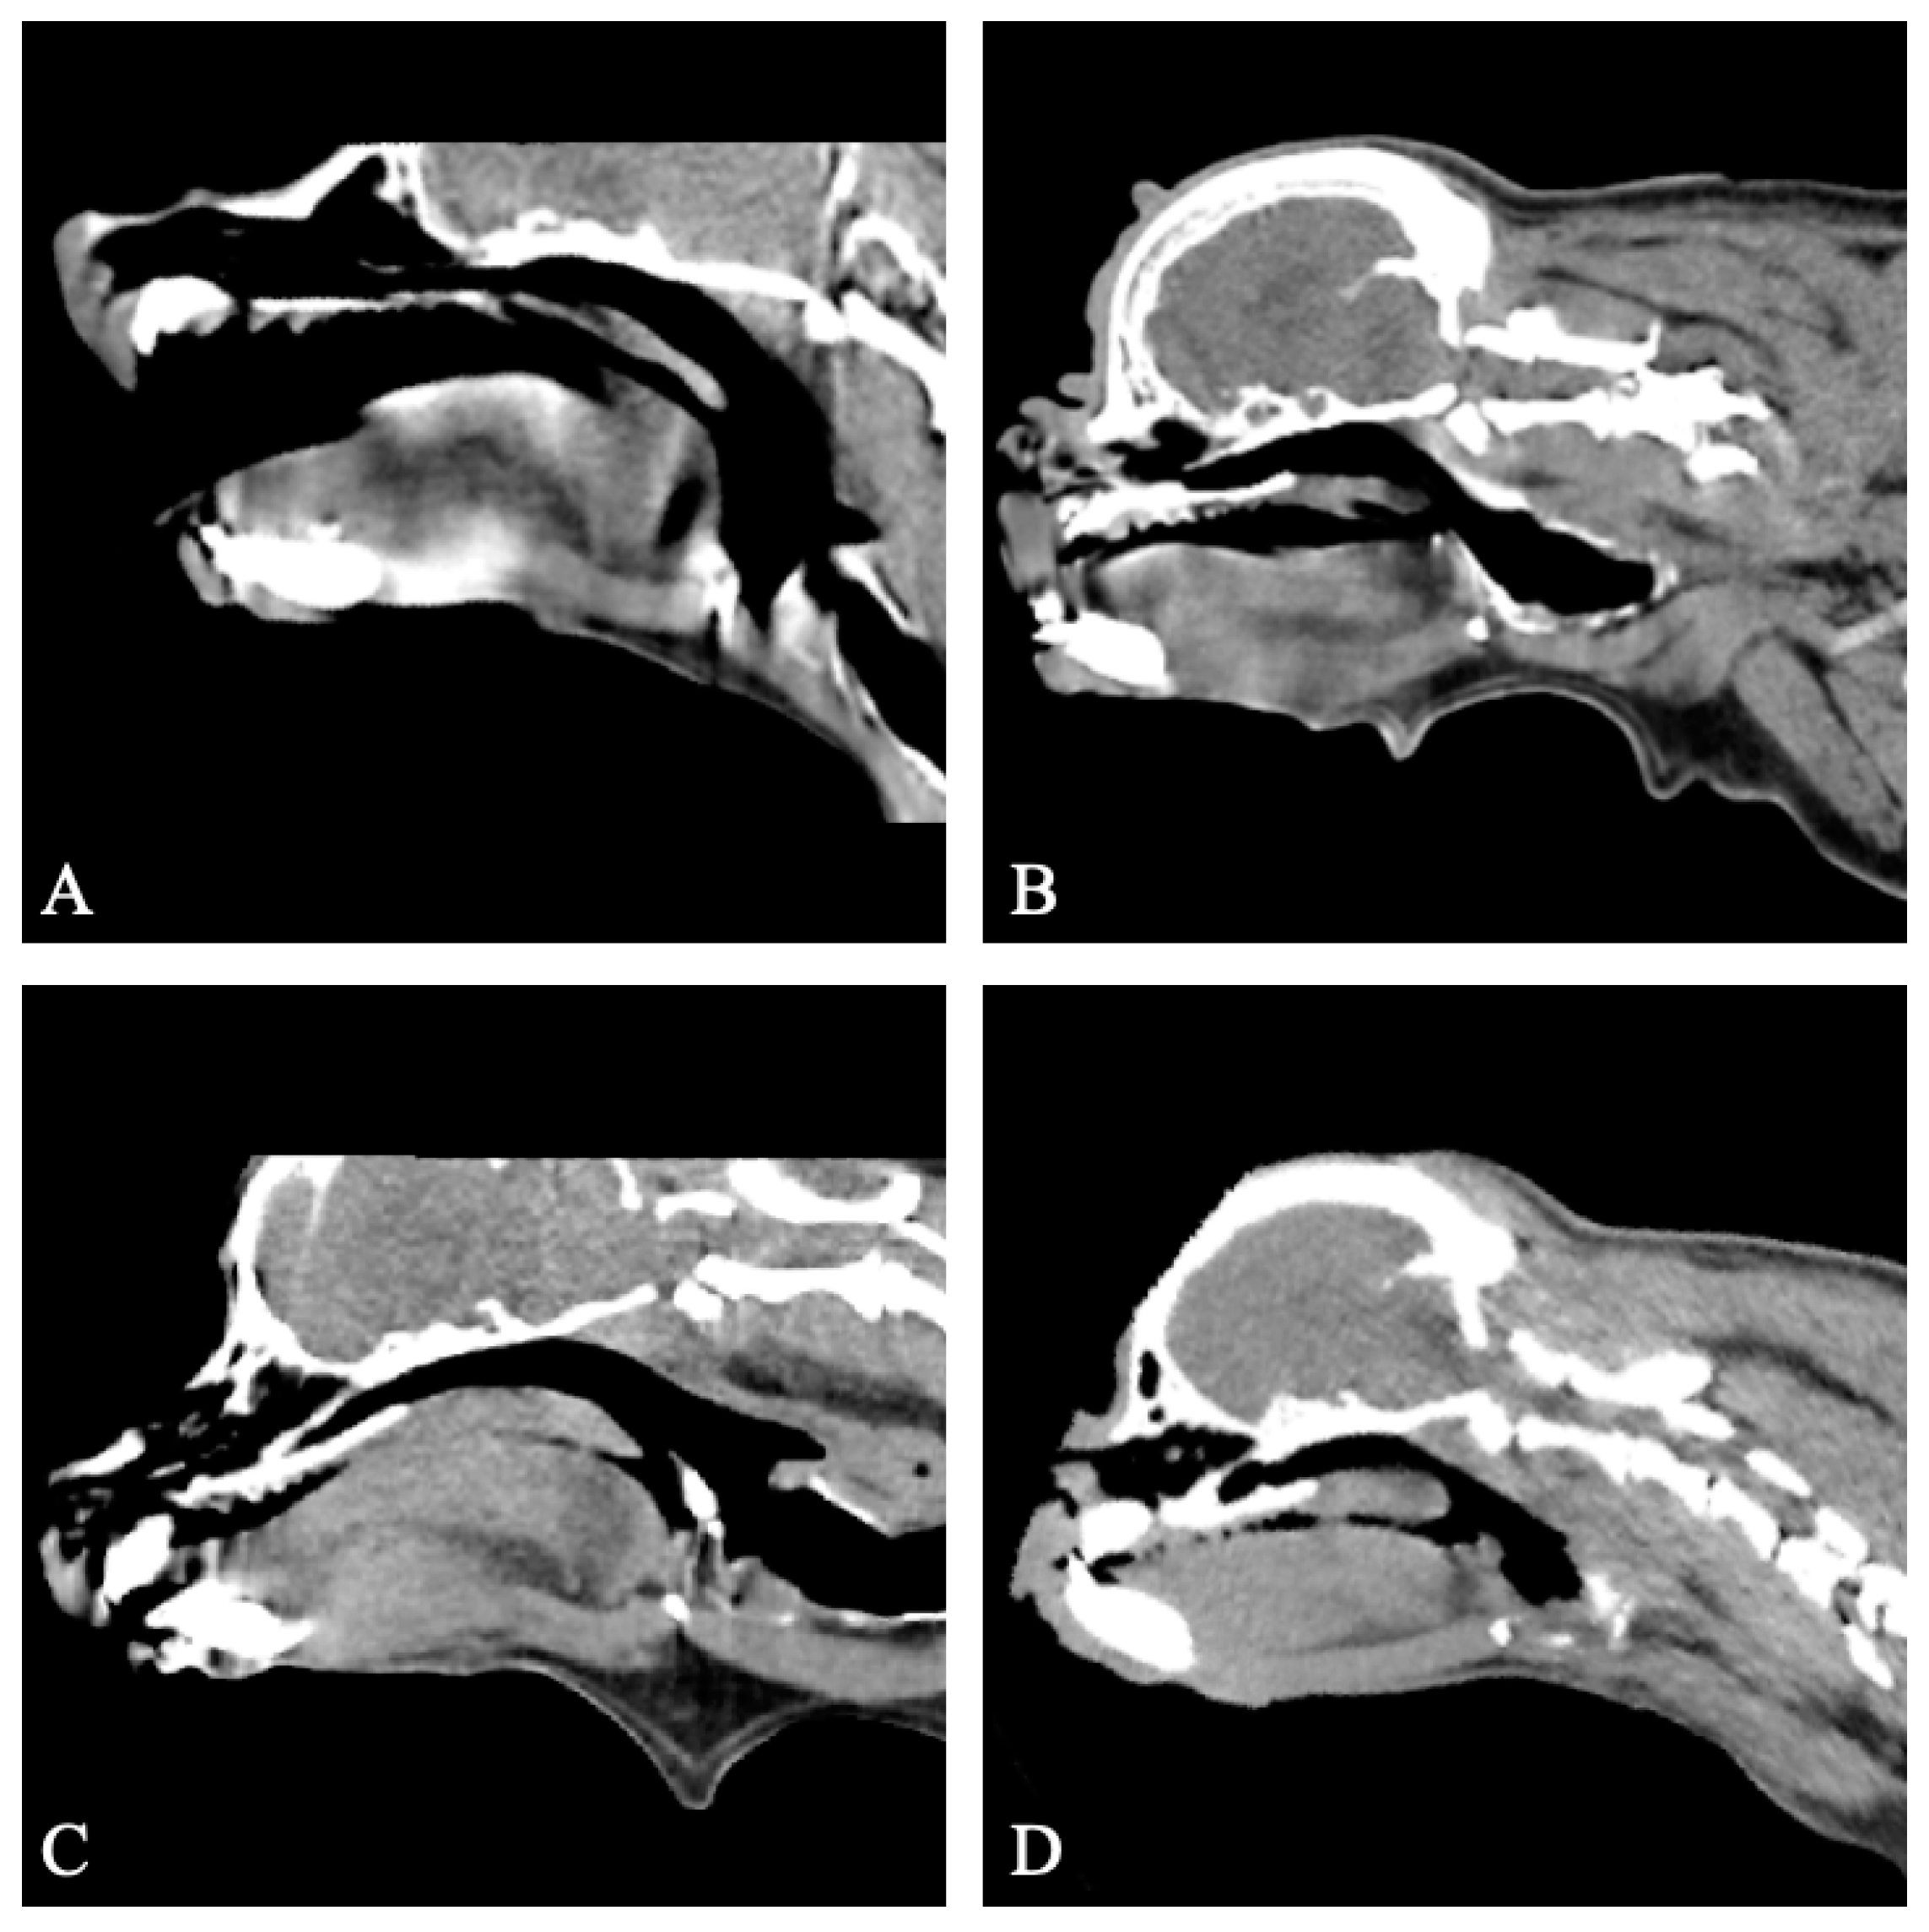

The CT provided diagnostic images for all seven patients for the evaluation of the soft palate and nasopharynx, with no motion artifacts in five patients, and moderate motion artefacts in two patients. All seven dogs displayed an overlong soft palate. Thickening of the soft palate was assessed as mild (n = 1), moderate (n = 3), and marked (n = 3) based on the extent of nasopharyngeal obstruction (Figure 2).

Figure 2. Sagittal non-contrast CT images of the skull of four patients with untreated brachycephalic obstructive airway syndrome (BOAS) (group I). All patients are displaying an overlong soft palate. All patients display varying degrees of soft palate thickening. (A) Case 6, mild soft palate thickening. (B) Case 3, moderate soft palate thickening. (C) Case 10, moderate soft palate thickening. (D) Case 9, marked soft palate thickening. Note the good visualisation of the soft palate despite motion artefacts in image C. Window width, 400 HU; window level 40 HU; 1 mm slice thickness.